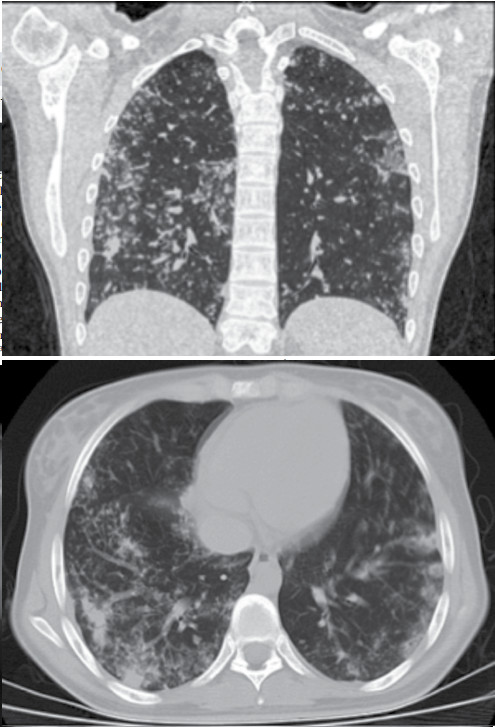

inferiores. TAC de tórax con múltiples micronódulos de aspecto

de árbol en gemación en ambos campos pulmonares (

figura 2,

Figuras 2 y 3. TAC de tórax

2. Corte coronal 3. Corte sagital.

Micronódulos pulmonares en aspecto de árbol

de gemación (flechas)